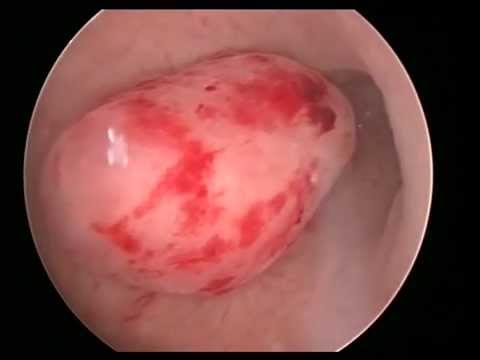

2)Histeroskopik Polipektomi veya Myomektomi :

Polip, rahim iç tabakasından ( endometrium ) kaynaklanan rahim içerisindeki alanı daraltan ve adet kanamasının fazla olmasına neden olabilen “et parçası” olarak tanımlanabilecek bir yapıdır. Normal yollarla veya tüp bebek uygulacak hastalarda gebelik şansını azaltacağı düşünülüyorsa histeroskopiyle çıkartılır.Hastanın kanama veya çocuk isteği olsun olmasın, poliplerin %1’inde kanser olasılığı olduğu için cerrahi olarak çıkarılması ( histeroskopik polipektomi ) ve çıkan parçaların mutlaka patolojiye gönderilmeleri önerilir.

Myomlar rahimin kas tabakasından (myometrium) kaynaklanan iyi huylu tümörlerdir. İç tabakaya yerleşen(submüköz) veya orta tabakadan kaynaklanan ( İntramural ) ancak iç tabakaya bası yapan myomlar, adet kanamasının fazla olmasına ve kansızlığa, çocuk isteyen hastalarda gebelik oluşmamasına, düşük ve erken doğum riskinin artmasına yol açabilirler. Bu nedenle histeroskopik myomektomi yapılır.

Histeroskopik polip eksizyonu

Histeroskopik myomektomi